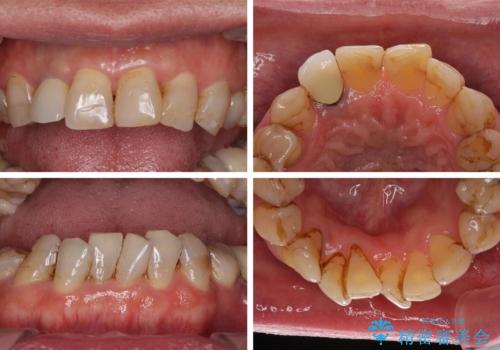

- 前歯のデコボコや、奥歯を咬んだときに痛みがあるとのことで来院された患者様です。

全体的に問題が多く、全てをしっかりと治療したいとのことでした。

全体的に中等度の歯周病と診断されたため、歯周外科処置やインプラントによる咬合回復から進めて行き、矯正治療による歯列改善を行った後にオールセラミッククラウンにて補綴することとしました。